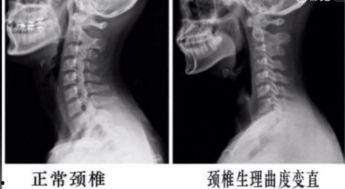

你知道吗,颈椎可是人体非常重要的部位哦!它不仅支撑着我们的头部,还负责传递大脑和身体之间的信息。但是,由于现代生活方式的改变,很多人都在不知不觉中伤害了它。所以,了解颈椎的重要性,是我们开始运动的第一步。